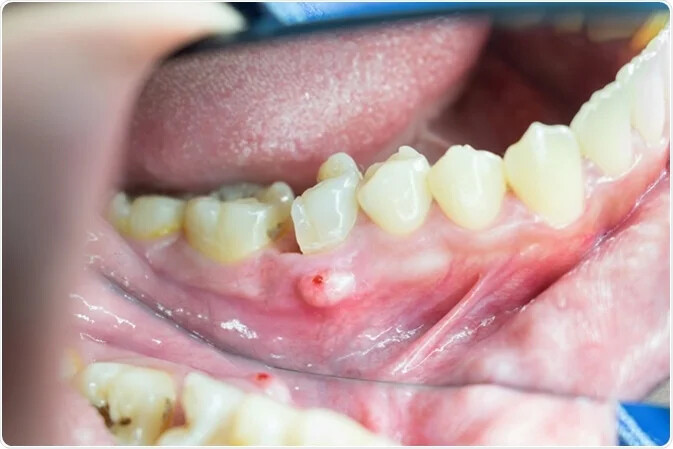

Apical periodontitis refers to the inflammation of the periodontium — the tissue that surrounds your teeth. Apical means "relating to the apex," so inflammation usually occurs around the tip — or apex — of the tooth's root. Two types of apical periodontitis exist:

Symptomatic. Symptomatic apical periodontitis causes pain and discomfort when a person bites down or makes contact with the surrounding teeth. This type of apical periodontitis is usually acute, meaning it comes suddenly and gets worse quickly. However, it can also be chronic.

Typically, apical periodontitis occurs when there's another problem with the tooth. For example, inflammation can develop if a person has an untreated cavity. In some cases, apical periodontitis can develop if the pulp of the tooth becomes infected or dies. Injury or trauma to the tooth can also lead to apical periodontitis.

Apicoectomy. If the infection develops or continues after the root canal, you might require an apicoectomy. During this procedure, the endodontist removes the tip of the tooth's root and infected tissue, then seals the end of the root with a filling.